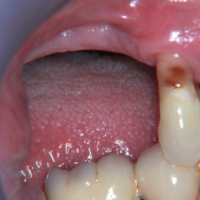

La paziente accusa fastidio generalizzato alle gengive con saltuario dolore in alcuni distretti, sanguinamento spontaneo e alla spazzolatura, difficoltà nelle manovre igieniche, difficoltà masticatoria, estetica insoddisfacente. Le immagini cliniche e radiografiche (Figg. 1-7) mostrano come il risultato finale sia dovuto a non corretta formulazione del piano di trattamento e a non corretta esecuzione delle procedure chirurgiche e protesiche. Il posizionamento errato degli impianti nei tre piani dello spazio comporta l’esposizione delle spire, in particolare sul versante vestibolare, impedendo la formazione di una ampiezza biologica adeguata a preservare l’osso peri-implantare. La mancanza o la scarsità di gengiva aderente costituisce ulteriore fattore di aggravamento del quadro. Noi sappiamo che per poter eseguire una implantologia in un unico tempo dobbiamo essere in presenza di una adeguata banda di mucosa aderente (Warrer et al 1995; Schrott et al 2009).

- Fig. 1 – Quadro clinico di mucosite perimplantare iatrogena: colletti implantari esposti, protesi incongrua, scarsità di mucosa aderente, sanguinamento spontaneo e indotto

- Fig. 2 – Quadro clinico di mucosite perimplantare: la protesi incongrua non permette le pratiche di una corretta igiene. Il sondaggio evidenzia la presenza di spire esposte sotto la mucosa, che appare sottile, scollata dalle superfici implantari e scarsamente cheratinizzata